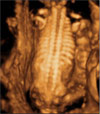

Ecografía 4D del tercer trimestre: Manos y pies de un feto

Ecografía 4D de las manos y pies de un feto en el tercer trimestre de embarazo

La curiosa imagen ecográfica en rotación de este bebé nos muestra claramente sus extremidades superiores y inferiores. De una de las manos podemos contar hasta las falanges. También se observa parte de la cara y del cordón umbilical, que rodea uno de los pies.